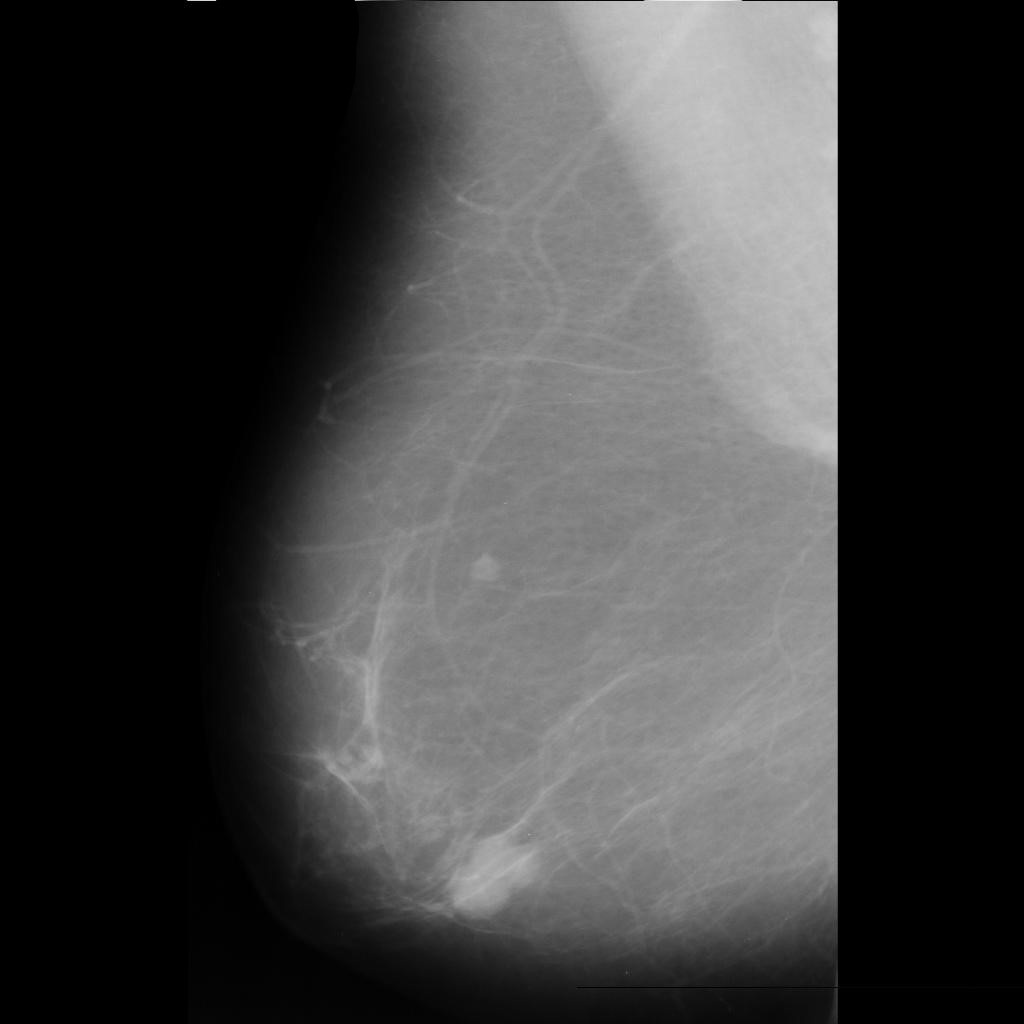

benign

malignant